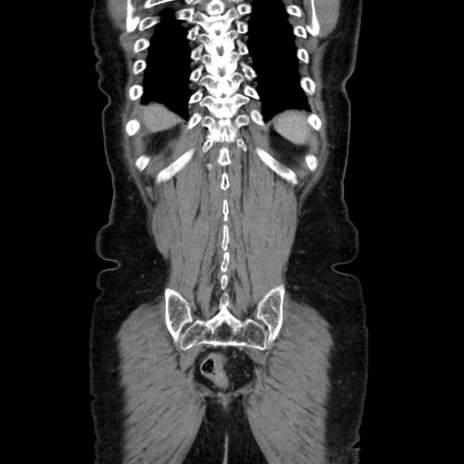

横断像

【症例】70歳代女性

【主訴】お腹が張る

【現病歴】1週間くらい前から腹部膨満の自覚あり。昨日夜から増悪したため、本日救急外来受診。

【身体所見】意識清明、BT 36.5℃、BP 165/106mmHg、HR 80bpm、SpO2 98%、腹部:膨満、軟、自発痛・圧痛なし、触診にて不快感あり、腸蠕動音:減弱

【データ】WBC 12600、CRP 1.04